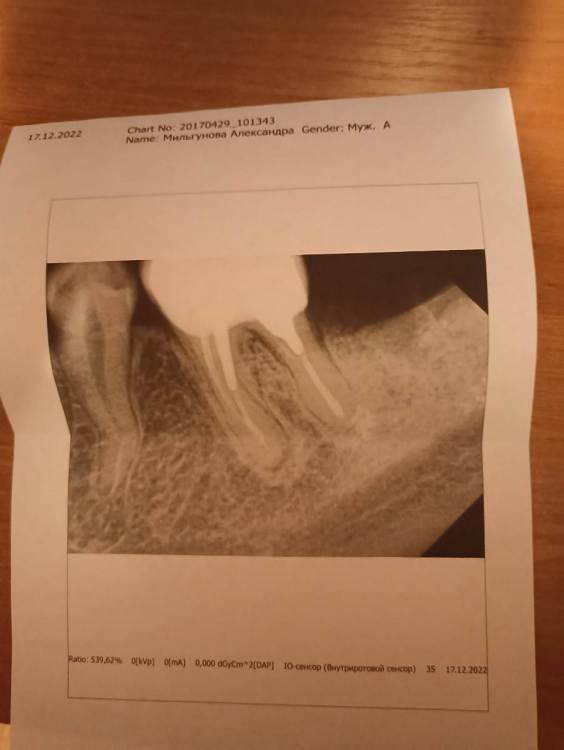

Саша М Опубликовано 20 декабря, 2022 Поделиться Опубликовано 20 декабря, 2022 (изменено) Здравствуйте! Хотела бы проконсультироваться. У меня очень болит 6 нижний зуб. Я только неделю назад взяла зуб под коронку и мне сказали, что изначально там всё хорошо с корнями. Но зуб начал сильно болеть после того, как мне поставили коронку. Когда врач брала зуб под коронку, мне сказали, что там всё хорошо и нет никакого воспалительного процесса. Сейчас мне предложили делать уколы Линкомицина, уже 2 укола сделали. Не знаю, может ли лекарство подействовать в такой ситуации. И что потом делать с зубом, если это не поможет? Мне предложили только удалить зуб или поговорить с хирургом. Может ли хирург разрезать десну и попытаться вычистить инфекцию в десне. Насколько это эффективно в такой ситуации? Не хочется терять зуб, так как 7ку недавно удалила. Может там что то другое болит, не из за воспаления? Прикрепляю снимок, может там ещё что-то не так на снимке. Пожалуйста, подскажите, что делать в такой непростой ситуации! Изменено 20 декабря, 2022 пользователем Саша М Ссылка на комментарий

IvanK Опубликовано 24 декабря, 2022 Поделиться Опубликовано 24 декабря, 2022 Здравствуйте, шансов на лечение у этого зуба очень мало. Думаю, что пора уже его заменить на имплантат 1 Ссылка на комментарий